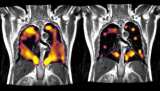

新成像技术可帮助发现长期新冠患者的隐性肺损伤

据外媒报道,一种新型影像技术能够检测到长期新冠对患者的肺损伤情况。由于这种损伤在标准的MRI或CT扫描中是看不到的,所以检测出这种肺功能减弱将有助于临床医生了解在长期新冠患者中所看到的持续呼吸障碍。 2021-05-27 产业应用